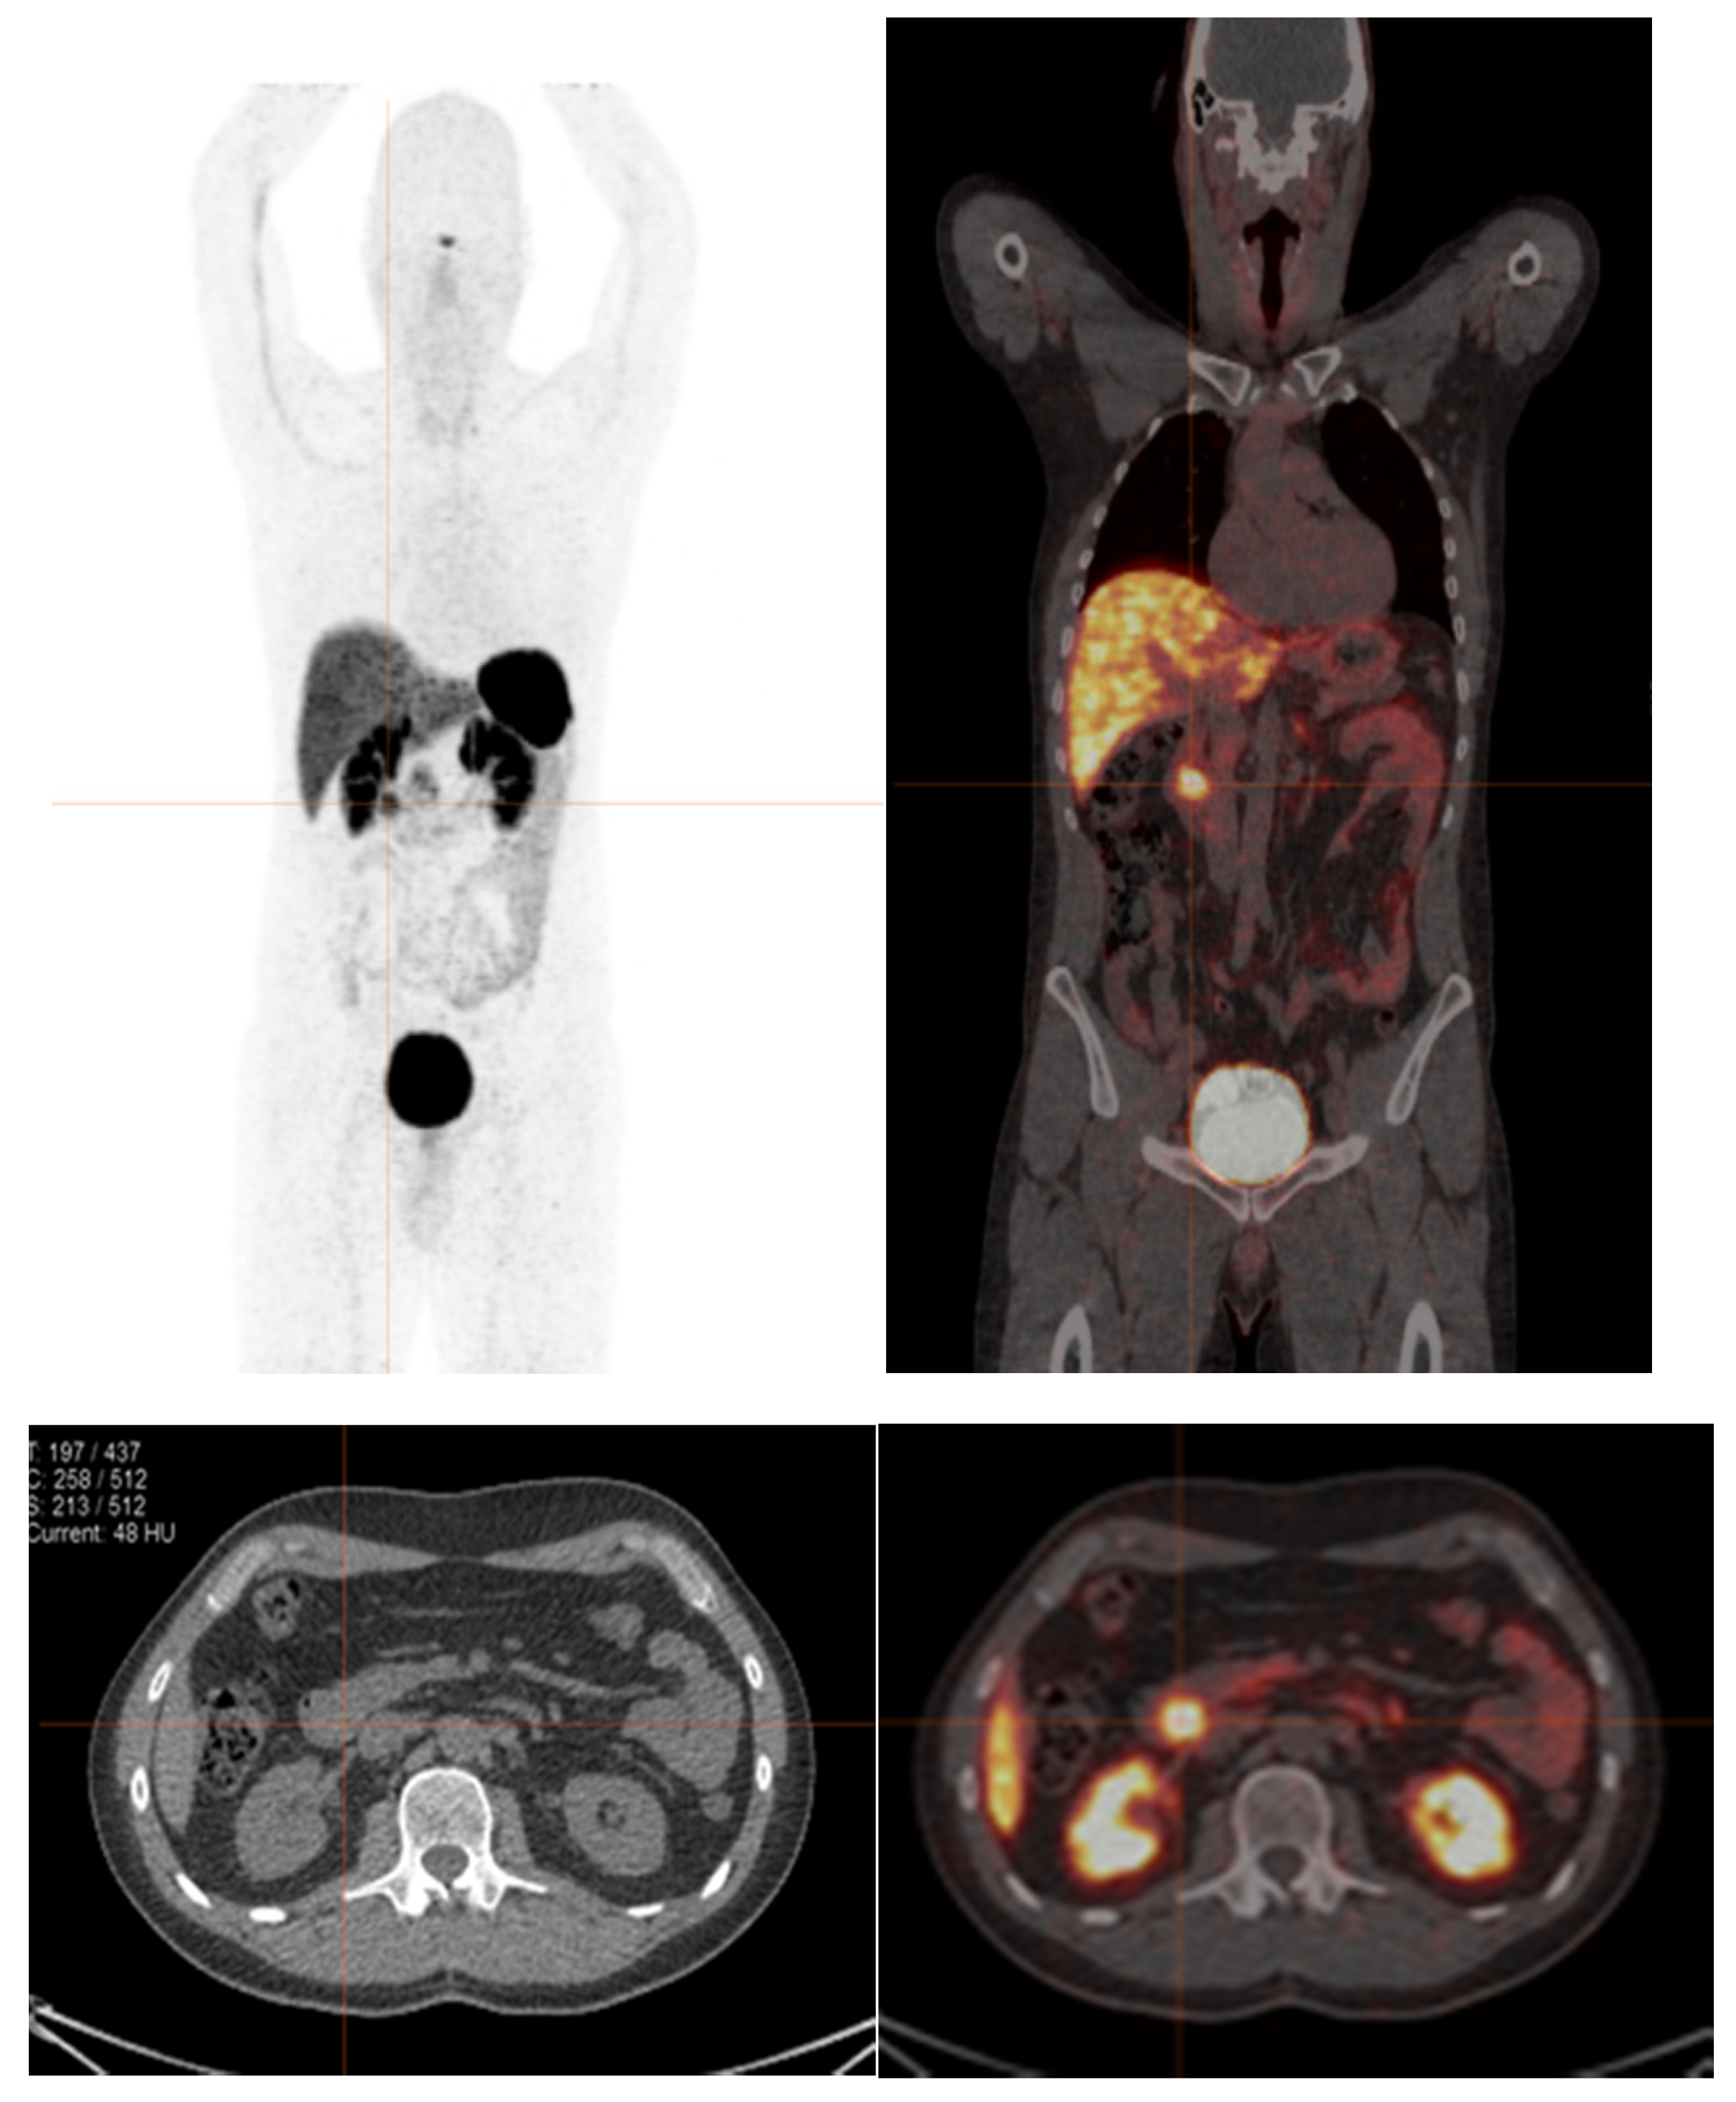

- Kayani, I.; Bomanji, J.B.; Groves, A.; Conway, G.; Gacinovic, S.; Win, T.; Dickson, J.; Caplin, M.; Ell, P.J. Functional imaging of neuroendocrine tumors with combined PET/CT using 68Ga-DOTATATE (DOTA DPhe1,Tyr3octreotate) and 18F-FDG. Cancer 2008, 112, 2447–2455. [Google Scholar] [CrossRef]

- Naswa, N.; Sharma, P.; Gupta, S.K.; Karunanithi, S.; Reddy, R.M.; Patnecha, M.; Lata, S.; Kumar, R.; Malhotra, A.; Bal, C. Dual tracer functional imaging of gastroenteropancreatic neuroendocrine tumors using 68Ga-DOTA-NOC PET-CT and 18F-FDG PET-CT: Competitive or complimentary? Clin. Nucl. Med. 2014, 39, e27–e34. [Google Scholar] [CrossRef]

- Zhang, P.; Yu, J.; Li, J.; Shen, L.; Li, N.; Zhu, H.; Zhai, S.; Zhang, Y.; Yang, Z.; Lu, M. Clinical and Prognostic Value of PET/CT Imaging with Combination of 68Ga-DOTATATE and 18F-FDG in Gastroenteropancreatic Neuroendocrine Neoplasms. Contrast Media. Mol. Imaging 2018, 26, 2340389. [Google Scholar] [CrossRef]